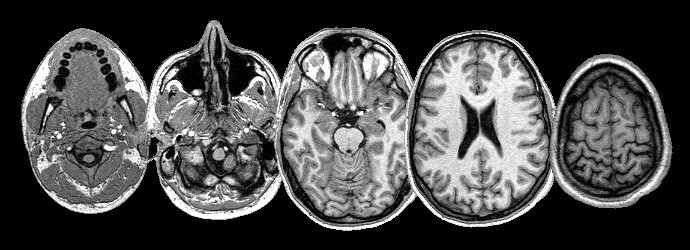

Op dit moment wordt aan Radboud Universiteit wetenschappelijk onderzoek gedaan naar taalfunctie in de hersenen na een hersenletsel: "Wij zoeken gezonde volwassenen tussen de 50 en 78 jaar die rechtshandig en niet claustrofobisch zijn, Nederlands hebben als moedertaal, en geen metalen voorwerpen hebben in het lichaam die niet uit kunnen (zoals beugels, bruggen implantaten). De gegevens van gezonde proefpersonen worden vergeleken met de gegevens van patiënten met een hersenbeschadiging. Deelname duurt 4 uur in totaal (2 bezoeken van ongeveer 2 uur aan de Radboud Universiteit). Tijdens deze afspraken wordt u gevraagd taaltaken uit te voeren terwijl uw hersenactiviteit wordt gemeten met MEG en MRI. Uw gegevens blijven geheel anoniem. Voor het meedoen krijgt u een onkostenvergoeding van €40. Bent u geïnteresseerd in deelname of heeft u vragen? Neem gerust contact op met Ileana Camerino () of Vitoria Piai ()."